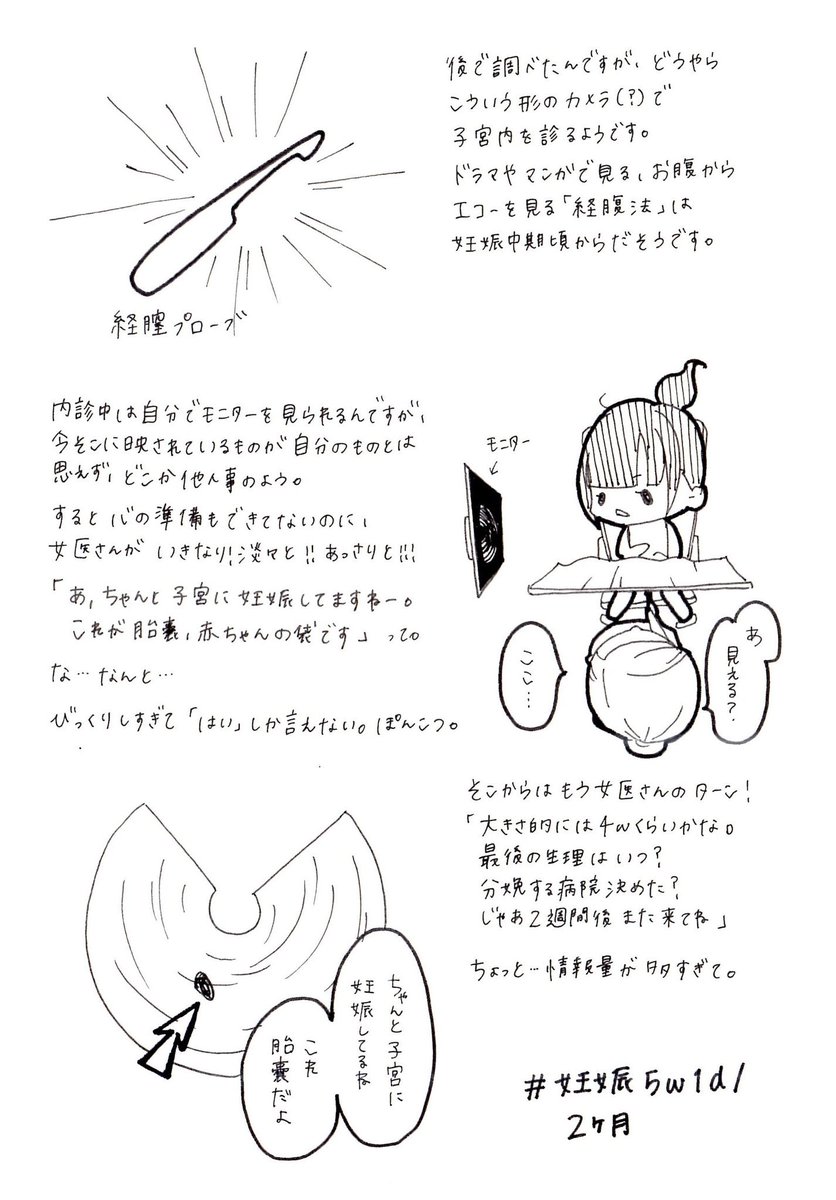

2018.8.7① 人生初の産婦人科受診。 #育児漫画 #育児日記 #妊娠 #妊娠初期 pic.twitter.com/Twdzx7vLye

2018.8.7② 人生が180度変わった瞬間。 #育児漫画 #育児日記 #妊娠 #妊娠初期 pic.twitter.com/MvxxnhDa3v